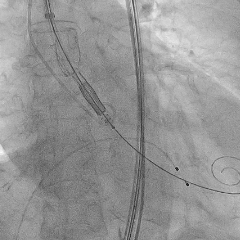

定位件释放

定位件入窦后造影